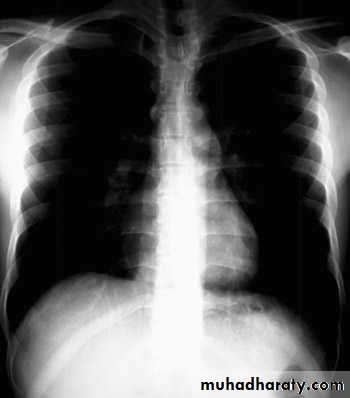

The vertebral bodies are just visible through the cardiac shadow

PenetrationLow KV

High KV